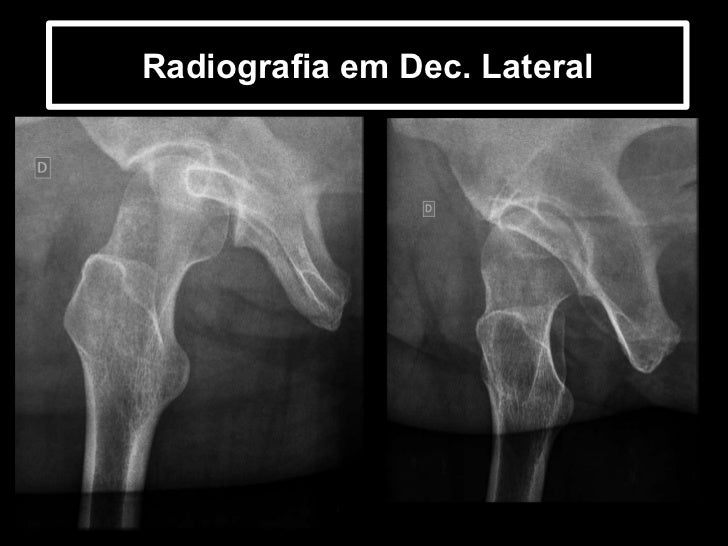

Radiografia em Dec. Lateral

73. 75. Radiografia em Dec. Lateral